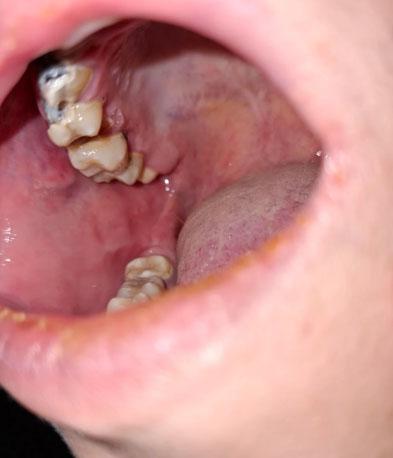

What Is Seen in This Case?

The image shows visible decay on back teeth (molars), with damaged tooth structure and discoloration. The surrounding gum tissue appears slightly irritated, which may indicate early inflammation caused by trapped bacteria.

Back teeth are more prone to decay because they are harder to clean and have deep grooves that trap food and plaque.

Based on the visual findings, the most likely conditions include:

Dental caries (tooth decay) on molars

Possible decay reaching the dentin layer

Early gum inflammation near the affected teeth

Risk of pulp infection if untreated

A dental examination and X-ray are required to determine how deep the decay has progressed.